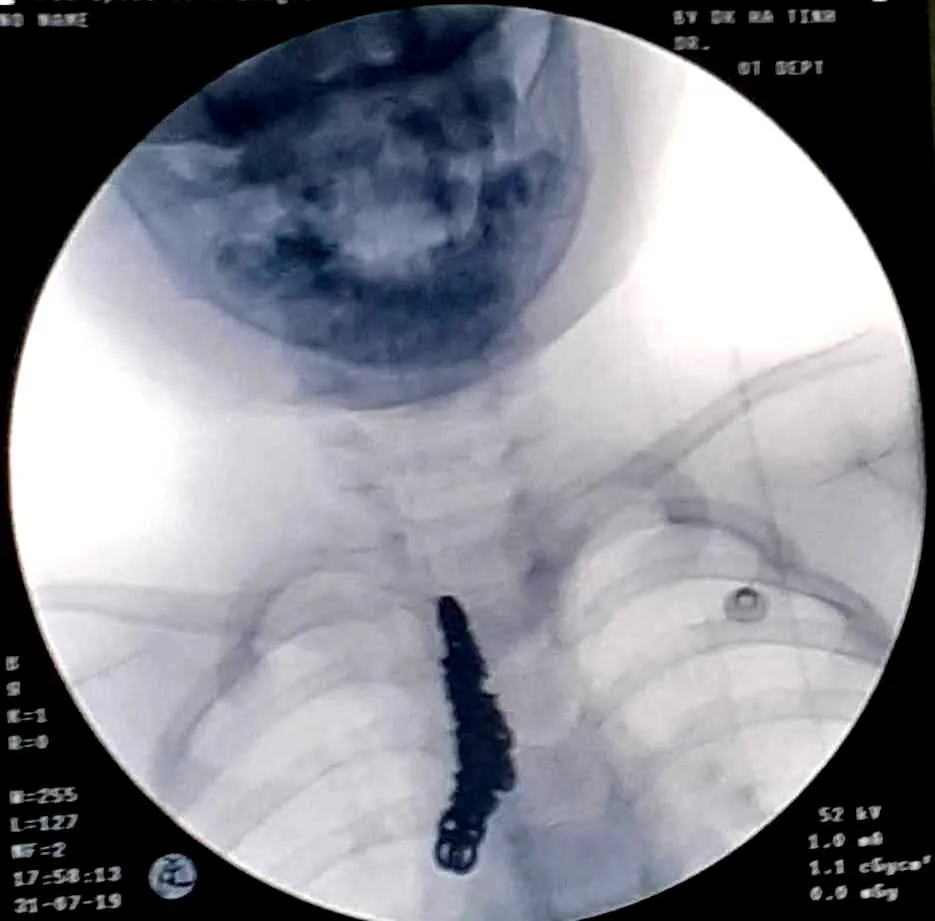

Sau khi thăm khám và chụp phim X-quang, các bác sĩ phát hiện hình ảnh cản quang bất thường tương ứng khí quản và một phần phế quản gốc bên phải của bệnh nhi H..

Gắp sợi dây chuyền bạc dài 14cm trong khí phế quản của bệnh nhi 28 tháng tuổi ảnh 1 Hình ảnh dị vật sợi dây chuyền được chụp qua phim